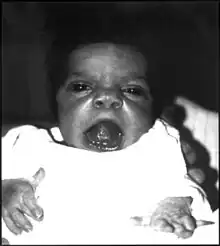

| An infant exhibiting the facial features of Robinow syndrome. | |

Robinow syndrome is an extremely rare genetic disorder characterized by short-limbed dwarfism, abnormalities in the head, face, and external genitalia, as well as vertebral segmentation. The disorder was first described in 1969 by human geneticist Meinhard Robinow,[1] along with physicians Frederic N. Silverman and Hugo D. Smith, in the American Journal of Diseases of Children. By 2002, over 100 cases had been documented and introduced into medical literature.[1]

Robinow noted the resemblance of affected patients' faces to that of a fetus, using the term "fetal facies" to describe the appearance of a small face and widely spaced eyes.[1] Clinical features also may include a short, upturned nose, a prominent forehead, and a flat nasal bridge. The upper lip may be "tented",[1] exposing dental crowding, "tongue tie", or gum hypertrophy.

Though the eyes do not protrude, abnormalities in the lower eyelid may give that impression. Surgery may be necessary if the eyes cannot close fully. In addition, the ears may be set low on the head or have a deformed pinna.[1]